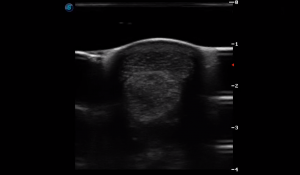

SIMON Ultrasound Database

This ultrasound database is a free resource for students and doctors!

Our collection includes videos of dogs, cats, horses, cows, humans, and many other species!